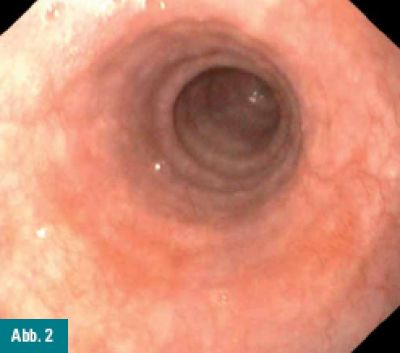

Bei einem 64-jährigen Patienten wird im Rahmen einer

Routinegastroskopie im proximalen Ösophagus ein Areal entdeckt, das

durch mehrere winzige, polypoide Erhabenheiten auffällt, während die

umgebenden Areale unauffällig imponieren.

Abbildung 1 und 2: Weißlichtendoskopie des proximalen Ösophagus, das linke Bild zeigt die makroskopischen Auffälligkeiten.